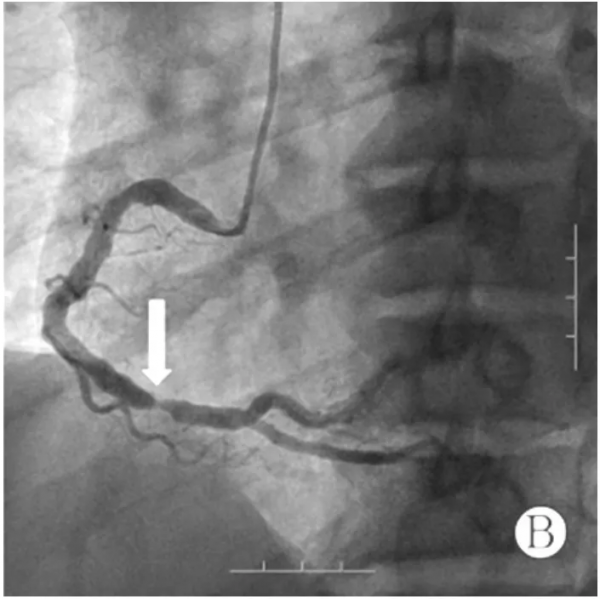

入院後即刻完善準備行急診冠狀動脈造影,顯示右優勢型冠狀動脈,前降支自中段第一對角支發出後100%閉塞,見圖2A;中間動脈近段侷限性狹窄50%,右冠狀動脈較粗大,第二轉折稍遠處侷限性狹窄95%,見圖2B。立即開通罪犯血管,經右側橈動脈入路,使用6F EBU3.5指引導管將BMW導絲順利透過閉塞段,常規預擴張後植入3 mm×18 mm支架一枚,並給予後擴張,即刻效果理想,見圖2C。此時患者一般狀況良好,生命體徵平穩,無任何不適症狀,考慮手術操作簡單,右冠狀動脈血管粗大且病變重,故一併處理,保留導絲並更換6 F JR4指引導管,仍使用BMW導絲並常規預擴張,順利植入4 mm×14 mm支架一枚,並給予後擴張,即刻效果理想,見圖2D;處理右冠狀動脈共使用3 min,造影劑10 ml,順利結束手術,術後給予水化治療及強化抗栓治療。

注:A 為前降支完全閉塞(箭頭所示),B 為右冠狀動脈重度狹窄(箭頭所示),C 為前降支被開通, D 為右冠狀動脈狹窄被解除

圖 2 患者冠狀動脈造影及 PCI 影象